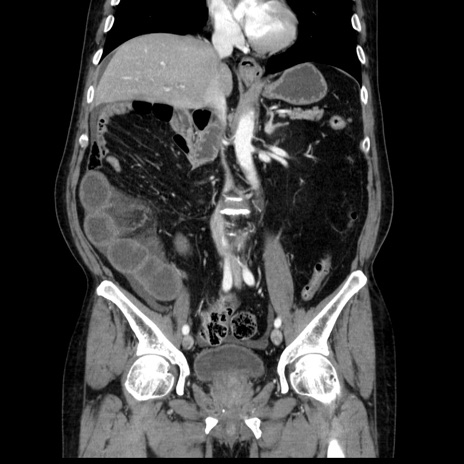

横断像

【症例】80歳代男性

【主訴】臍周囲痛

【現病歴】約6時間前から臍下部痛が出現。次第に腹部膨隆・背部痛も生じてきたため来院。背部痛の場所は変化しない。

【身体所見】意識清明、BT 36.3℃、BP  131/87mmHg、P 87bpm、SpO2 100%(RA)、臍周囲自発痛・圧痛あり、反跳痛なし、自発痛部位に一致して板状硬あり、腹部膨隆、腸雑音減弱、CVA tenderness両側陰性。

【データ】WBC 19600、CRP 0.33